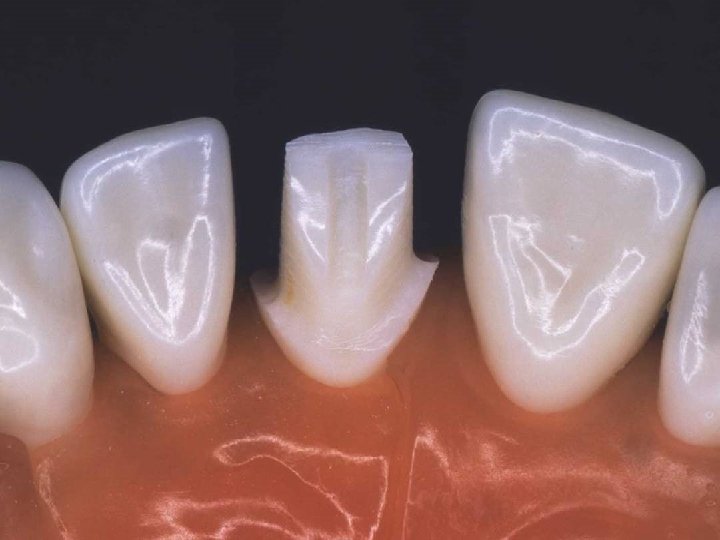

Axial wall and shoulder finishing

PREPARATION STEPS l Incisal (Occlusal) Reduction l Facial Reduction l Lingual Reduction l Finishing